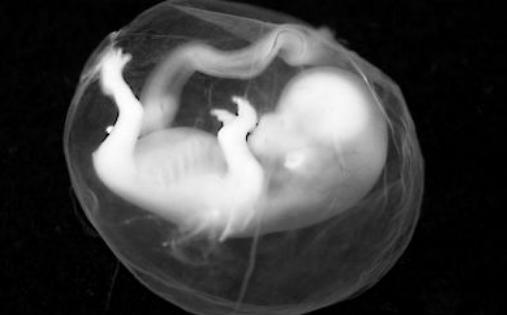

就在上个月,宋女士已经怀孕32周了,却忽然觉得身体不适,赶快去医院做检查,医生发现宋女士肚子里面的胎儿有点不正常,就赶快安排她做了一个B超。

医生的诊断结果,让宋女士悲痛不已,胎儿已经没了心痛,成了死胎。其实,前几天宋女士就有点感觉,由于家里别较忙,胎儿也是有时动有时不动,就没有太在意,谁想到一时大意就成了悲剧。

胎儿是通过脐带与母体进行影响输送的,如果准妈妈吸入了有害气体,肯定会影响胎儿的发育,一旦发生缺氧对婴儿非常不利,轻则大脑智力受到影响,严重的时候真的有可能会胎死腹中。

孕中晚期发生的突然没有胎心,则有可能为胎儿缺氧所致,如脐带病变:脐带扭转、脐带脱垂等;如果母体病变:过期妊娠、妊高征、心血管疾病、中毒性休克等;也会导致胎盘供氧不足,使胎儿缺氧死亡。建议孕妇孕妇居室的环境一定要保持室内空气流通,一旦出现胸闷,气短等症状,一定要及时就医。